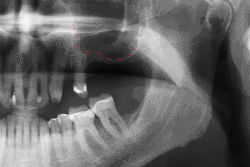

Для разрушения абатментных винтов (стрелка) в 3 имплантатах необходимо снять оставшуюся часть винта и заменить его.